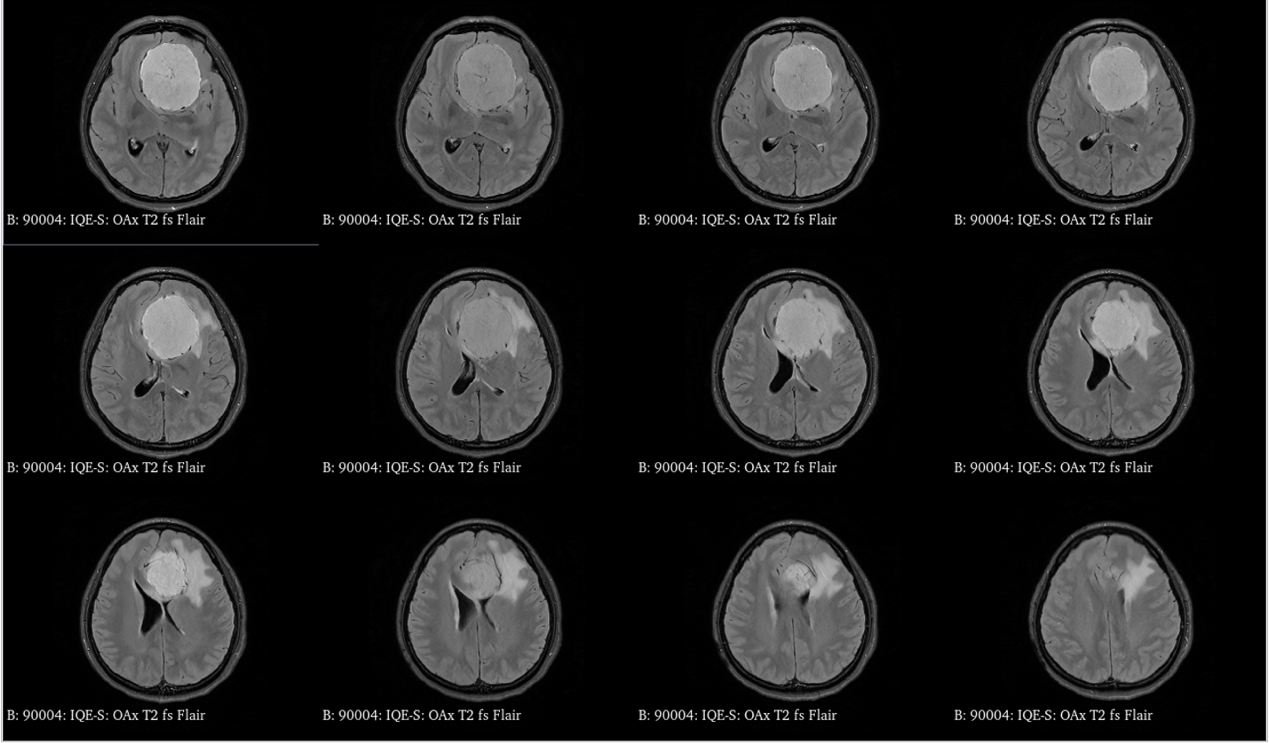

青年女性,因“左眼失明10个月,头痛3个月”就诊我院。

入院诊断:颅内占位病变(前颅窝底)脑膜瘤?;左眼失明;鼻炎

前颅窝底脑膜瘤常起源于前颅底筛骨筛板处的硬膜,瘤体多为双侧生长,少数为偏侧生长,女性稍多于男性。肿瘤可累及鸡冠和蝶骨平台的任何区域,是前颅窝肿瘤中最多见的一种。因为肿瘤位于前颅窝底,额叶在功能上属于“哑区”,患者就诊发现肿瘤时瘤体多已巨大。主要症状可有颅内压增高症状、视力减退、癫痫以及精神症状等。该患者主因“左眼失明10个月,头痛3个月”就诊。术中采用双额冠状开颅,左侧为主,由于肿瘤体积巨大,术中切除少许薄层额叶脑组织,边离断基底、边瘤内减压,分块切除肿瘤,最终探查肿瘤基底主要位于鸡冠、筛板、蝶骨平台、鞍结节、前床突处硬膜,术中见肿瘤供血主要来源于前颅窝底硬膜及大脑前动脉分支,术中仔细辨认供血动脉、过路血管,大脑前动脉及其分支保护完好,术中见视神经、视交叉受压明显,尤其是左侧视神经已缺血苍白,最终达Simpson II级切除。术者体会,该患者术前行多模态重建,可见瘤表数条粗大的静脉,术中切莫过早离断肿瘤的引流静脉,以防因引流不畅致瘤体肿胀出血;术前行多模态重建,利于鉴别供血动脉、过路血管,早期离断供血动脉更利于肿瘤切除;该类肿瘤基底一般较为广泛,不能盲目离断基底,尤其是近鞍结节处,可以于中线处离断基底,进入第一间隙后向两侧探查并保护视神经,待充分缩小瘤体看清楚毗邻的血管神经后再将其完全切除;术毕做好多层颅底重建以防脑脊液漏。另外,该患者术前左眼失明已达10个月,术后第1天即有光感,术后1月复查左眼视力可达50cm内数指,这在临床中非常少见,对于此类病人,不要轻易放弃挽救视力的任何机会。